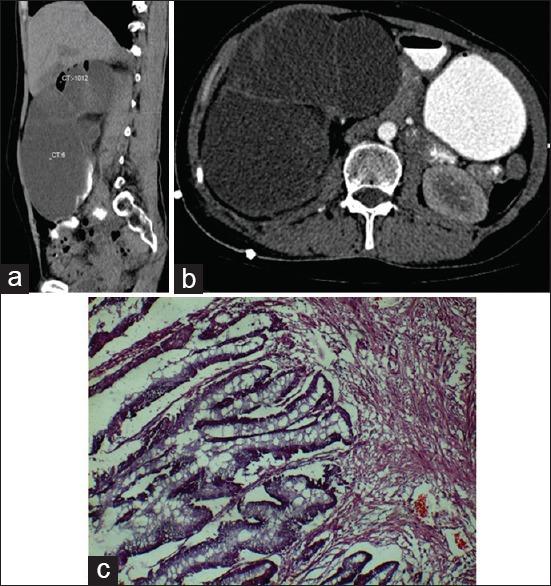

Presentation of mucinous adenocarcinoma of renal pelvis masquerading as gross hydronephrosis: A histopathological surprise.

South Asian J Cancer. 2017 Apr-Jun;6(2):78. doi: 10.4103/2278-330X.208838.